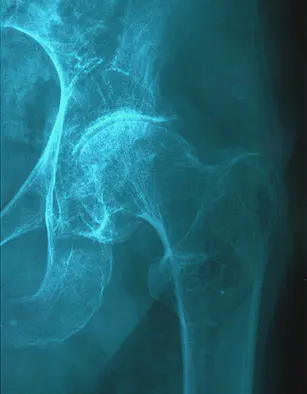

Le sport pour prévenir les fractures du col du fémur

La fracture du col du fémur est l’une des causes principales de la perte d’autonomie pour les personnes âgées. Alors pour prévenir ces fractures, il faut bouger pour renforcer ses os et son équilibre. La fracture du col du fémur est toujours une mauvaise aventure "à risque" ?

- L’ostéoporose qui fragilise l’os.

- L’ostéoporose de type I per et post ménopausique (trabéculaire) responsable surtout de tassements vertébraux.

- L’ostéoporose plus tardive (trabéculaire et corticale) de type II responsable des fractures du col du fémur.